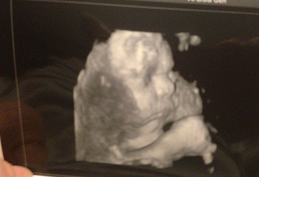

Today we had another NST/AFI, mom went with me and we had the NST first. Per her standard Emma was buzzed... lol... this little girl I tell ya... One of these days she wont be buzzed I just know it. She cooperated like she does and we were on our way. Our AFI went well too. Levels were at 18 which is GREAT! The kind ultrasound tech showed us our sweet girls profile, which I love, then she asked if we had to be anywhere to which we responded NOPE. She said oh good, your my last patient's and I want to flip to 3D. I've always wanted to get a 3D ultrasound but weren't sure we wanted to put out the money so I was ELATED. The pictures are AMAZING! They are so clear, we got to see her sweet face, and its confirmed she has Peters nose but my cheeks! Oh our sweet girl! I just love her so much!

Here are some 3D pics! Because at the end of the day she is what matters!

She looks like she is thinking... hmm... "How much longer am I stuck in here"